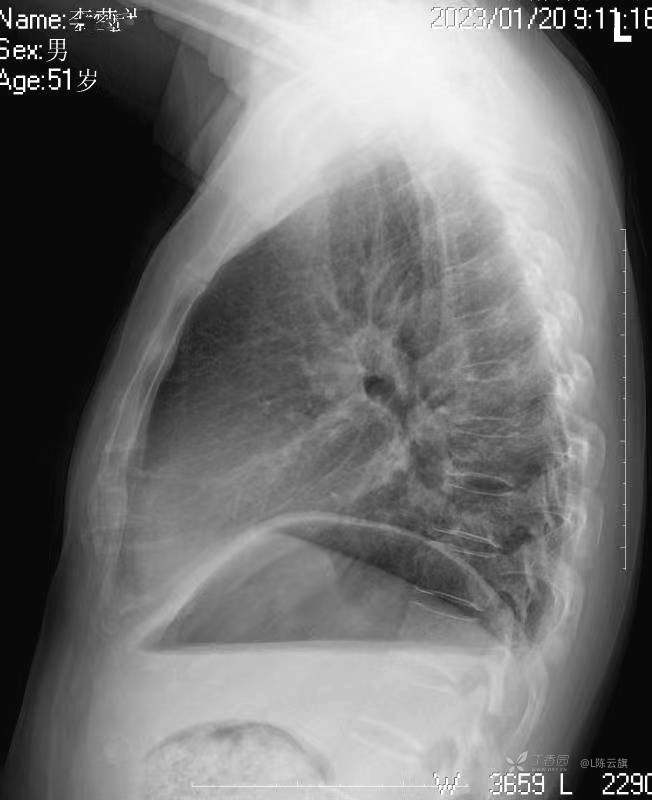

华夏览雄 达人已点赞1、患者男,51岁,精神病长期住院患者,主要病史只有时不时觉得腹部不适,其他不详。系列胸片为定期胸部检查。

3、根据系列复查胸、腹部平片的不同表现,你能否总结出什么征象和经验呢?